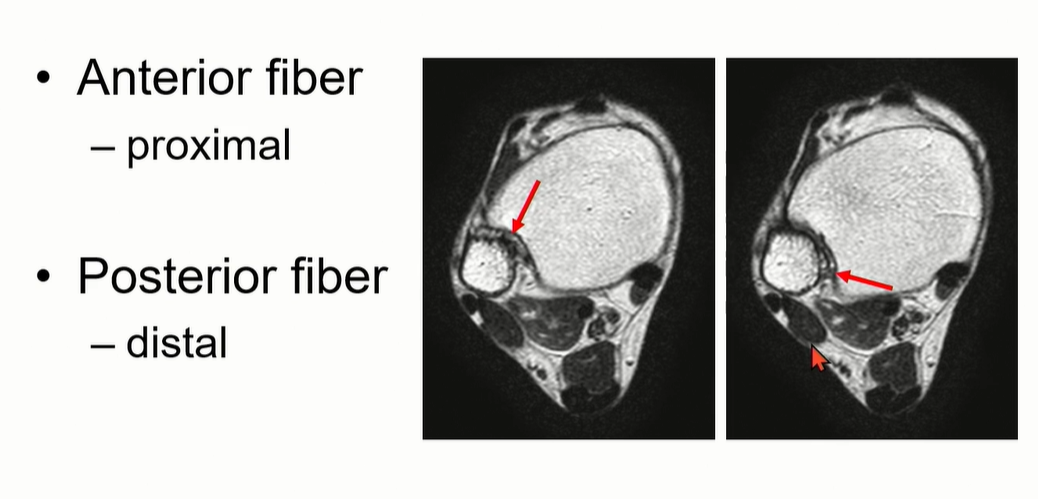

4-1. Interosseous Ligament

Anterior fiber가 proximal에 위치, posterior fiber가 distal에 위치하게 된다.

Tibia의 fibular notch와 fibula를 연결하는 역할을 한다.